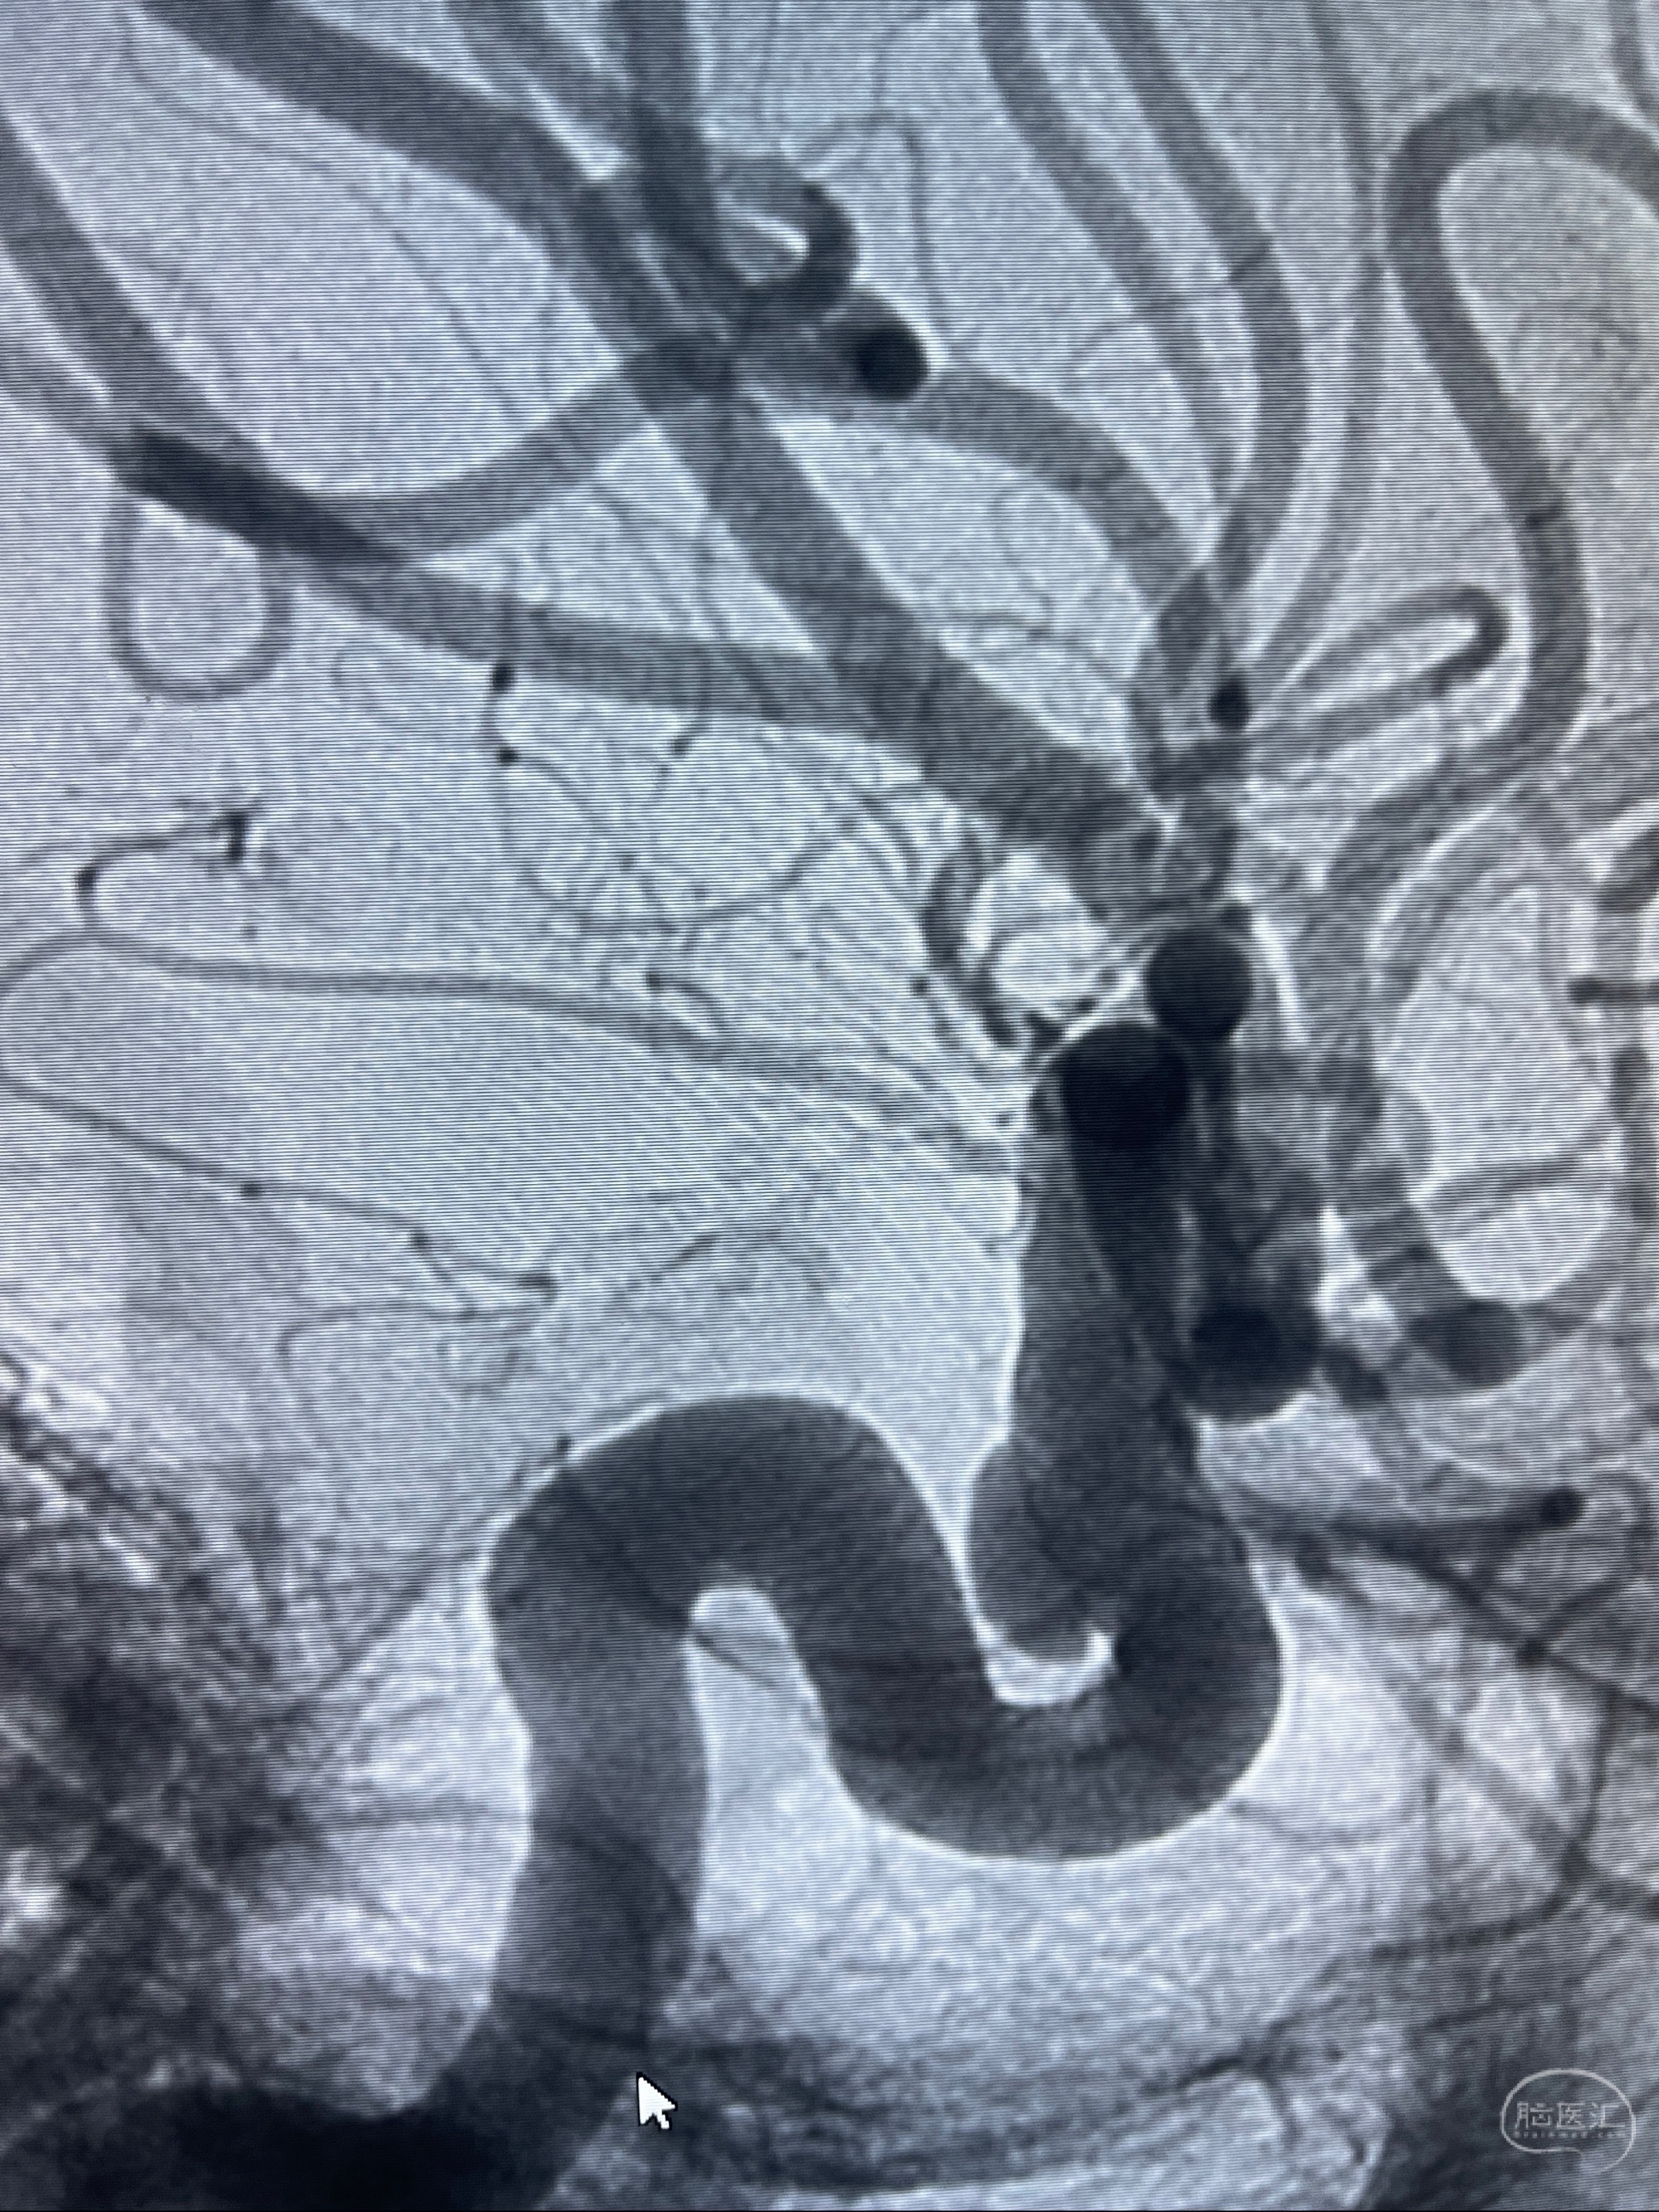

CTA示:右侧颈内动脉C6段见指向下方的突起,余左侧颈内动脉、双侧椎动脉、大脑前动脉、大脑中动脉、大脑后动脉及基底动脉走形正常,未见明显扩张及狭窄,局部未见明显瘤样扩张。

看原图,应该有两侧动脉瘤😅

2023-07-27全脑血管造影:双侧颈内动脉眼动脉段动脉瘤,右侧较大

2023-08-01全麻下行双侧颈眼动脉瘤支架辅助栓塞